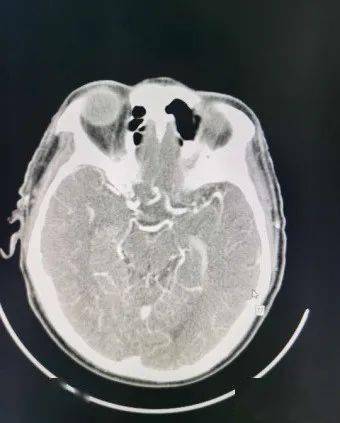

头颅cta图像

术前头部cta示大脑中动脉走形分支区域见增粗动脉血管影,局部呈结节状